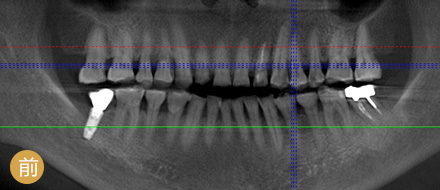

数字化精确导航种植

导航辅助种牙,创口小更舒服

• >智能导航,精确高效

• >适用症广,缺牙重生

• >避免盲种,成功率高

• >种牙精准,不伤神经